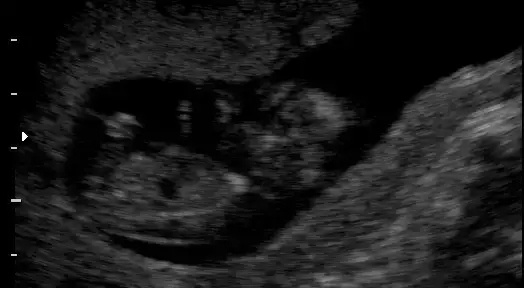

dr soylemeden siz gorun genital nub teorisi ( bebegin cinsiyeti)

$11+1.webp $12+3(2).webp $12+3.webp $13+2.webp

Resimlere tıkladığınızda haftaları yazıyo:emir_bebek::emir_bebek:

pek tecrubeli degilim..yani cok onemsemeyin ama bence erkek ;)

nub buyuk geldi banaaa..kizlar duzeltsinler ama bence erkek